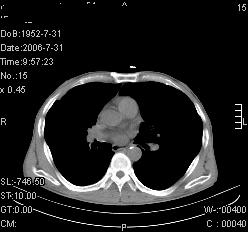

患者,男,54岁,咳嗦,咳痰20天。抗炎治疗2周。现esr76mm/h,目前患者症状明显好转,但发现两次ct片未见明显变化。两次分别做与7.25、7.31。第一次诊断右肺上叶炎症累计胸膜。大家看,从影像上内排除结核吗?

结核的可能性非常大,右上肺病变应该考虑干酪性肺炎。理由:

1.纵隔内多发淋巴结肿大。

2.esr76mm/h。

3.虽经抗炎治疗肺窗病灶有所吸收、减小,但纵隔窗病灶形态、密度、范围无明显变化。如果是单纯的大叶性肺炎,“抗炎治疗2周,目前患者症状明显好转”病灶应该基本消散了,至少也处于吸收消散期,密度变淡、范围变小。同时本病例所示其内的密度不均匀,见多发大小不一空洞样影也不符合大叶性肺炎吸收消散期表现。

病灶特点:片状 索条 结节混杂影,部分融合,密度不均,广泛累及相应胸膜.

临床治疗;二周未吸收.但症状好转.

多考虑:肺结核.